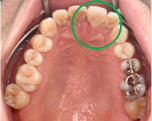

男性 Mさん 50代 (オールセラミック冠)

主訴

右上奥歯が、冷たいものにしみる。

治療内容

歯髄(神経および血管)まで到達する大きな虫歯でしたので、抜髄(歯髄を取り除く)をし、ファイバーコアをいれ、オールセラミック冠を被せました。

所感

現在、保険治療において、限定的ではありますが、大臼歯にも白い被せ物(プラスチック冠)ができるようになりました。しかし、実感としてプラスチック冠は、

- すり減りやすい。割れることがある。

- バイオフィルム(細菌およびそれから産生される副産物の塊)が付着しやすいので、歯周病および2次カリエス(被せ物と自分の歯の境目から再度虫歯になる)になるリスクが高い。

- 変色する。

という点を感じます。白い被せ物が保険の治療でできるという理由で、安易にプラスチック冠を選択し、割れたりすり減ったり、変色したらもう一度被せなおせばいいと考えるのであれば、一度立ち止まって考えてみてください。歯の量は、治療するたびに薄く少なくなり、歯根破折のリスクが高まります。もし大きな虫歯になってしまったら、最高レベルの根管治療をし、最良の被せ物であるオールセラミック冠を被せ、定期的にお口の中のクリーニングをし、同じ歯を2度と治療しないことが、歯を長持ちさせる最良の方法だと考えます。

オールセラミック冠(失活歯):¥104,500(税込)

Before

劣化したプラスチック冠